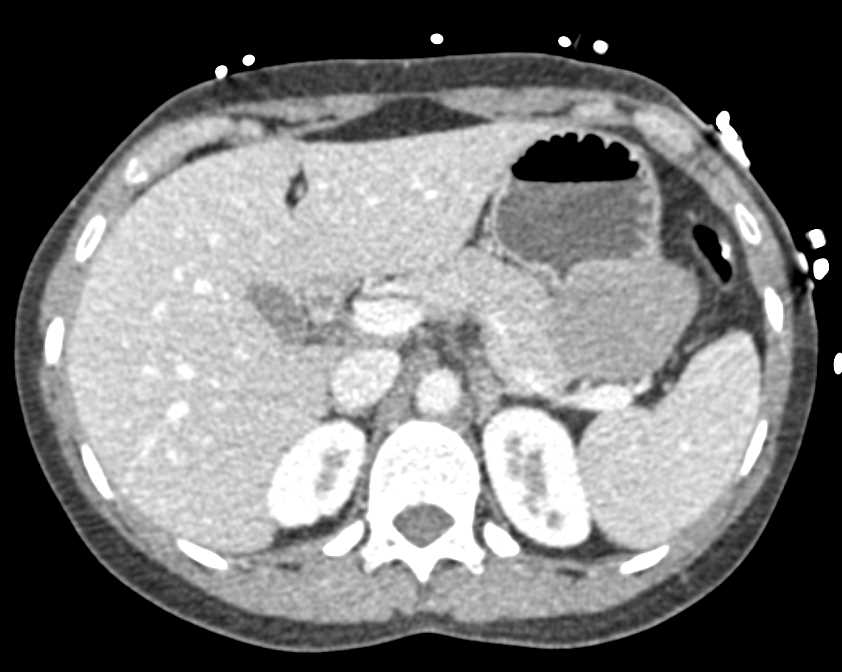

Mass Pushes on Tail of Pancreas was Ganglioneuroma